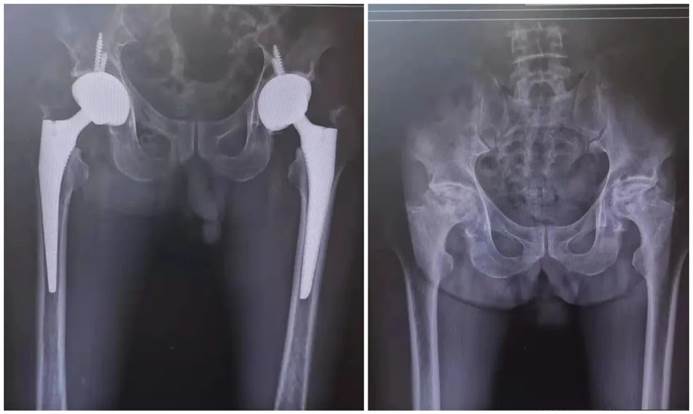

人工关节置换术:适用于关节疾病严重、无法通过保守治疗缓解的患者。该手术通过移除患者的受损关节部位,用人工关节替代受损关节,以恢复关节功能。随着科技不断创新和发展,人工关节置换术符合人体生物力学原理,能够最大程度减轻患者关节疼痛,挽救了中晚期严重的病变关节,使患者能够早期下床,早期改善负重,避免心肺功能衰竭、感染、压疮等临床并发症发生。

人工全髋关节置换术

人工全膝关节置换术